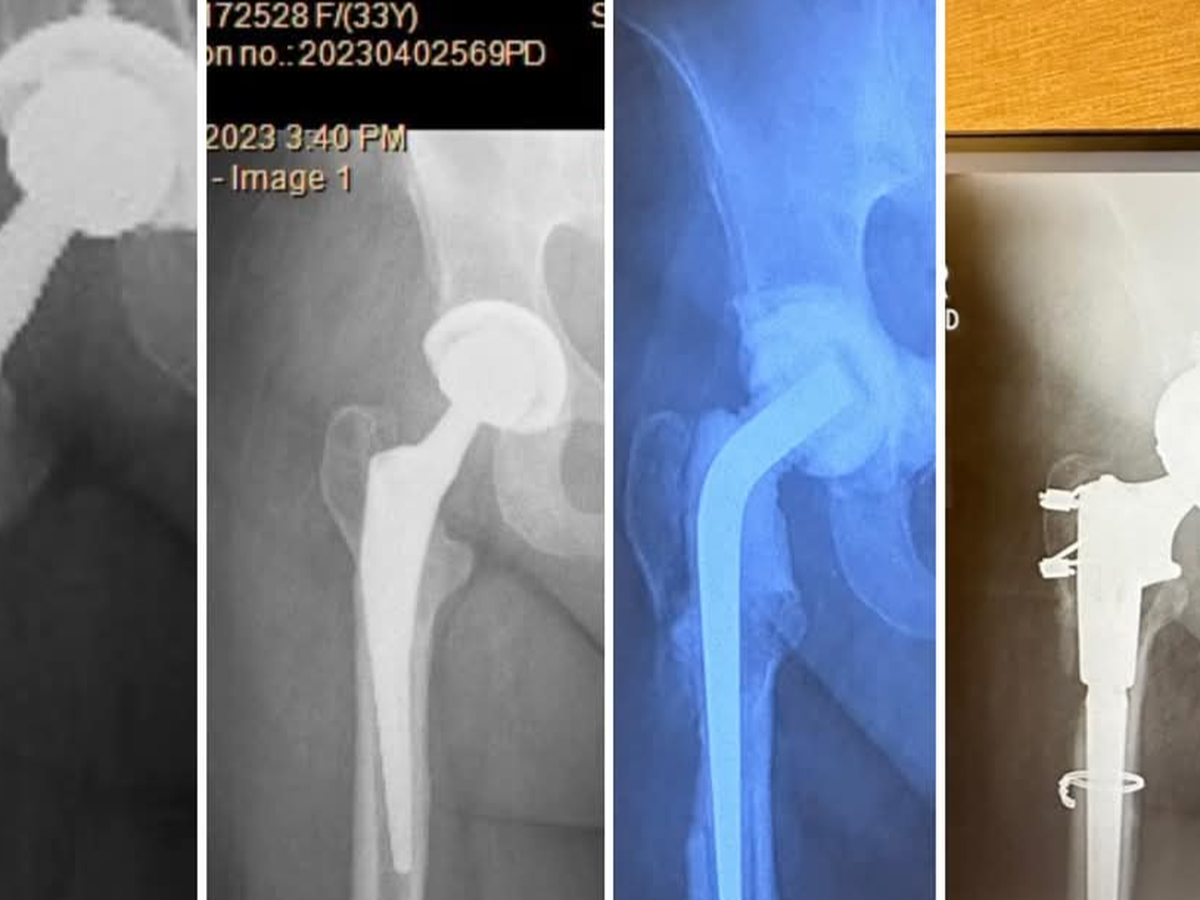

Nadine has endured living in constant pain since 2019 due to a misdiagnosed broken hip, and it's been a whirlwind of medical complications since. Nadine has undergone multiple hip replacements, all of which have needed to be removed and replaced due to recurring life-threatening infections caused by an under-functioning liver.